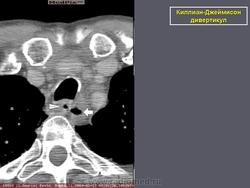

Киллиан – Джеймисон - дивертикул

Киллиан – Джеймисон - дивертикул.

Приложения:

0.radiographics_logo.png0.rg_.337125153.fig15advustoronnyaya_killian-dzhemison_divertikulov_v_76-letney_zhenshchiny.gif0.rg_.337125153.fig15bdvustoronnyaya_killian-dzhemison_divertikulov_v_76-letney_zhenshchiny.gif